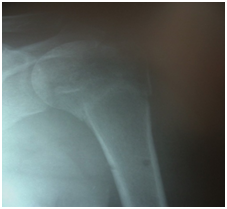

Figure 1 Pre-operative.

Figure 2 Immediate post-operative- Since this was initial of our patients, the greater tuberosity was not considered for fixation; however in our later cases, greater tuberosity was fixed as a rule.